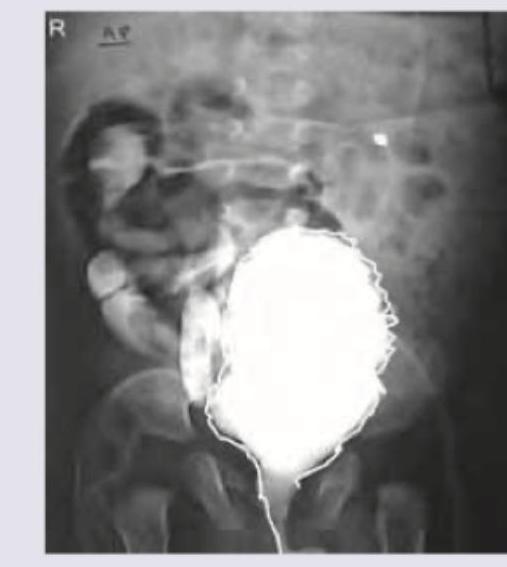

A 1 month old child with recurrent episodes of fever. On examination a suprapubic swelling was noticed and mother reports poor urinary stream. MCUG was performed. All are true about the condition shown except:

Comment on the diagnosis of the image shown below. (AIIMS Nov 2017)

A 3-year-old boy presents with occasional episodes of passing urine after very long durations, going up to as long as 12 hours. Since the child cries due to discomfort and then passes urine with straining, a VCUG is ordered. The VCUG image is shown below. What is the diagnosis?